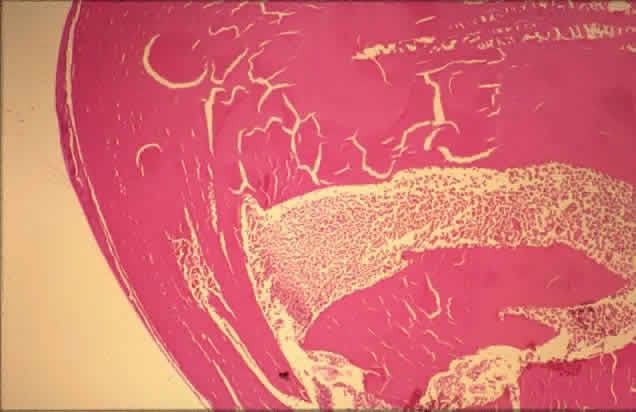

Radiant energy in the visible spectrum passes through the transparent retina and is absorbed by melanin pigment, hemoglobin, or both, depending on the wavelength chosen. The result is a focal scar of the outer retina, or if intense enough, full-thickness retina (Fig. 14).61 Full-thickness scars can cause extensive visual field loss because of obliteration of the nerve fiber layer.20

Fig. 14. Low-power view of panretinal photocoagulation. Normal retina is to the extreme right. Centrally there are areas of outer retinal loss (center arrows), and to the extreme left (single arrow) is an area of full-thickness retinal loss with migrated pigment epithelium. (H&E, × 19.5)